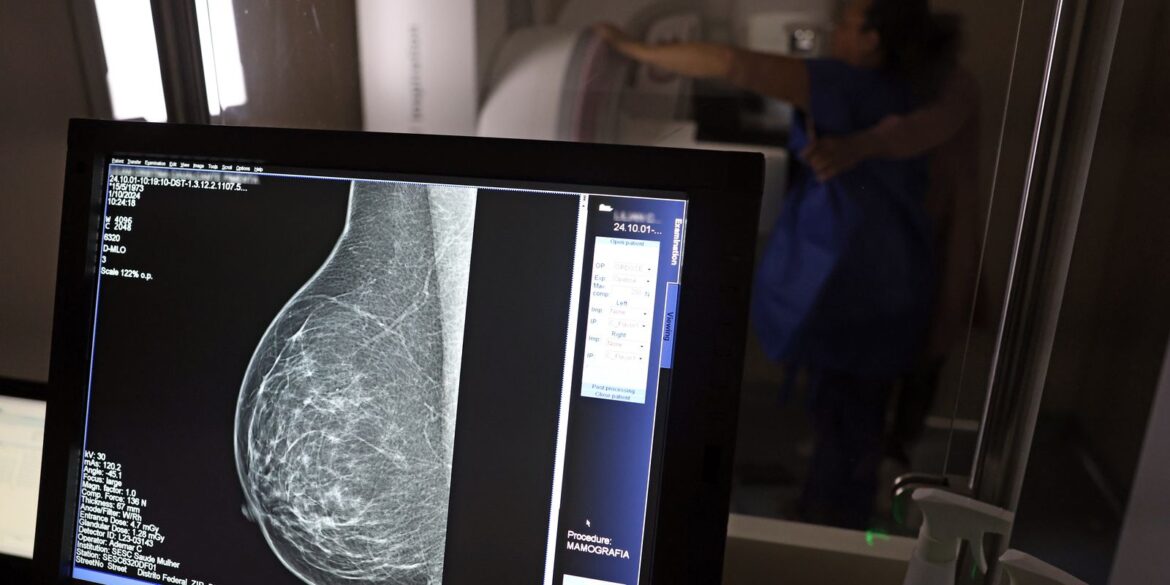

O Ministério da Saúde passou a recomendar o acesso a mamografia, via Sistema Único de Saúde (SUS), para mulheres de 40 a 49 anos – mesmo que não haja sinais ou sintomas de câncer de mama. De acordo com a pasta, a faixa etária concentra 23% dos casos da doença, e a detecção precoce aumenta as chances de cura.

Até então, a orientação era que o exame fosse feito a partir dos 50 anos.

A medida faz parte de um conjunto de ações anunciadas nesta terça-feira (23) voltado para a melhoria do diagnóstico e da assistência. A recomendação para mulheres a partir dos 40 anos é que o exame seja feito sob demanda, em decisão conjunta com o profissional de saúde.

“A paciente deve ser orientada sobre os benefícios e desvantagens de fazer o rastreamento. Mulheres nesta idade tinham dificuldade com o exame na rede pública de saúde por conta da avaliação de histórico familiar ou necessidade de já apresentar sintomas”, informou o ministério em nota.

As mamografias via SUS em pacientes com menos de 50 anos, de acordo com a pasta, representam 30% do total, o equivalente a mais de 1 milhão apenas no ano de 2024.